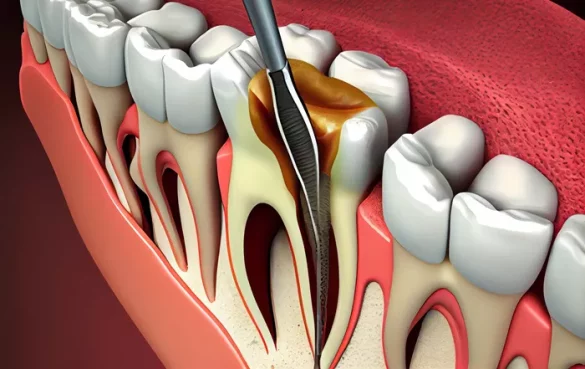

A root canal is a dental procedure that removes infected or damaged pulp from inside the tooth. The pulp contains nerves, blood vessels, and connective tissue. When the pulp becomes infected due to deep decay, gum disease, or trauma, it can cause pain, swelling, and abscess formation. A root canal eliminates the infection, preserves the tooth structure, and prevents the spread of bacteria to surrounding tissues.

Root canals are necessary when the tooth pulp is irreversibly damaged. Common causes include:

1. Quality of the Dental Procedure

The skill of the dentist or endodontist plays a major role. Accurate cleaning, shaping, and sealing of the root canals prevent bacterial leakage. If any part of the canal is missed, bacteria can remain and cause reinfection.